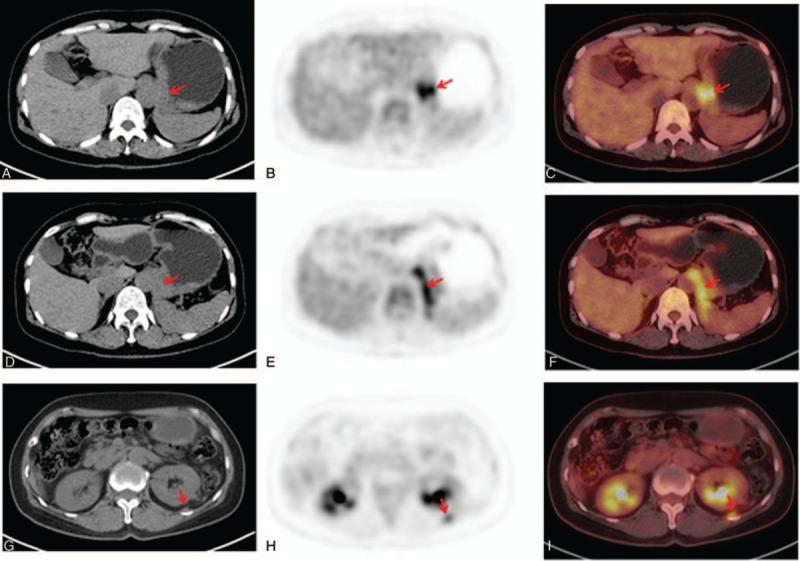

F-FDG PET/CT scan showed local thickening of the gastric wall, invasion of adjacent soft tissue, diaphragmatic and peritoneal metastasis at early stage, absence of regional lymph node metastasis, and increased F-FDG metabolism in primary tumor and metastatic tumor.

F-FDG PET/CT扫描显示胃壁局部增厚,早期侵犯相邻软组织、膈肌和腹膜转移,无区域淋巴结转移,原发肿瘤和转移瘤的F-FDG代谢增加。